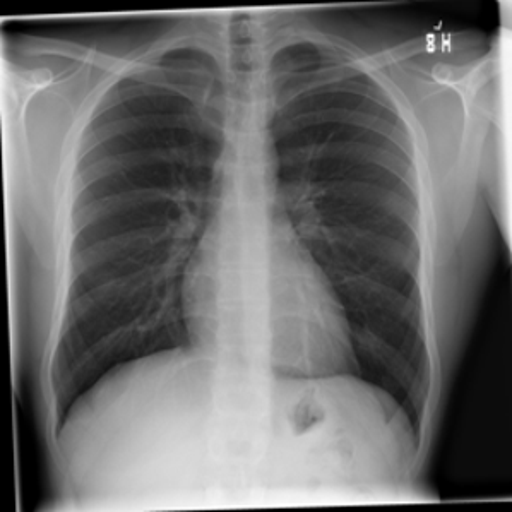

4.1 Qualitative Evaluation of Healthy Counterpart Generation

Example images from the disease COVID-19 Radiography Database and their generative healthy counterparts are given in figure 2. The images on the far left are instances of the lung opacity class from the real images in the dataset. The images in the middle column are examples of the generated healthy counterfactuals obtained via latent space diffusion, with RadBERT-guided textual-conditioning via a conditional prompt “normal chest x-ray”. A total of 75 diffusion inference steps are used with image conditioning strength=0.85 and guidance scale=7.5. (The former indicates the level of constraint on changes to the original input image and the latter is the weight given to the textual encoder conditioning in the generation of the image, ranging over [0,1] and [0,9], respectively).

Side-by-side inspection of the generated healthy counterfactuals (as per fig. 2) suggests that, as required, only minimal perturbation is made to the original image with respect to healthy pixels -i.e. localized image sites without structural medical defects. (In the top row, the medical structural defect in the original image is due to a lung opacity, and characterized via a relatively complex interaction between the imaging modality and subject manifesting as ‘gaps’ in the corresponding portions of the lung scan). The healthy/non-healthy discrepancy maps in all of these cases are obtained via masked subtraction of the original image from the generated image (the ground truth segmentation masks correspond to the broad area of interest –i.e. the complete lung). The generated healthy tissue is thus a subset of the mask and is shown in the final column of fig. 2 for the respective cases.

In the context of a VANT-GAN[20]-based approach, this highlighted material constitutes the diagnostic counterfactual visual attribution, i.e. the selection of material relevant to the diagnosis of the unhealthy condition. Healthy counterfactual generation was performed for the complete datasets in the three unhealthy classes, i.e Lung opacity, Viral Pneumonia and COVID, examples of which are given in fig. 3 for the three classes (all of the generated healthy counterfactuals from this experiment can be found on https://huggingface.co/ammaradeel/diffusionVA). Visual inspection indicates that the generated counterfactuals are, in general, visually plausible with minimal perturbation made to the unhealthy image overall. Moreover, the healthy counterpart generation does not appear to unnecessarily affect aspects of the images unrelated to the medical condition, the model selectively making changes to the unhealthy regions in a structurally plausible manner, e.g. generating missing portions of the lung without generating extraneous lung material where it would be expected to normally exist (e.g. in the abdominal cavity).